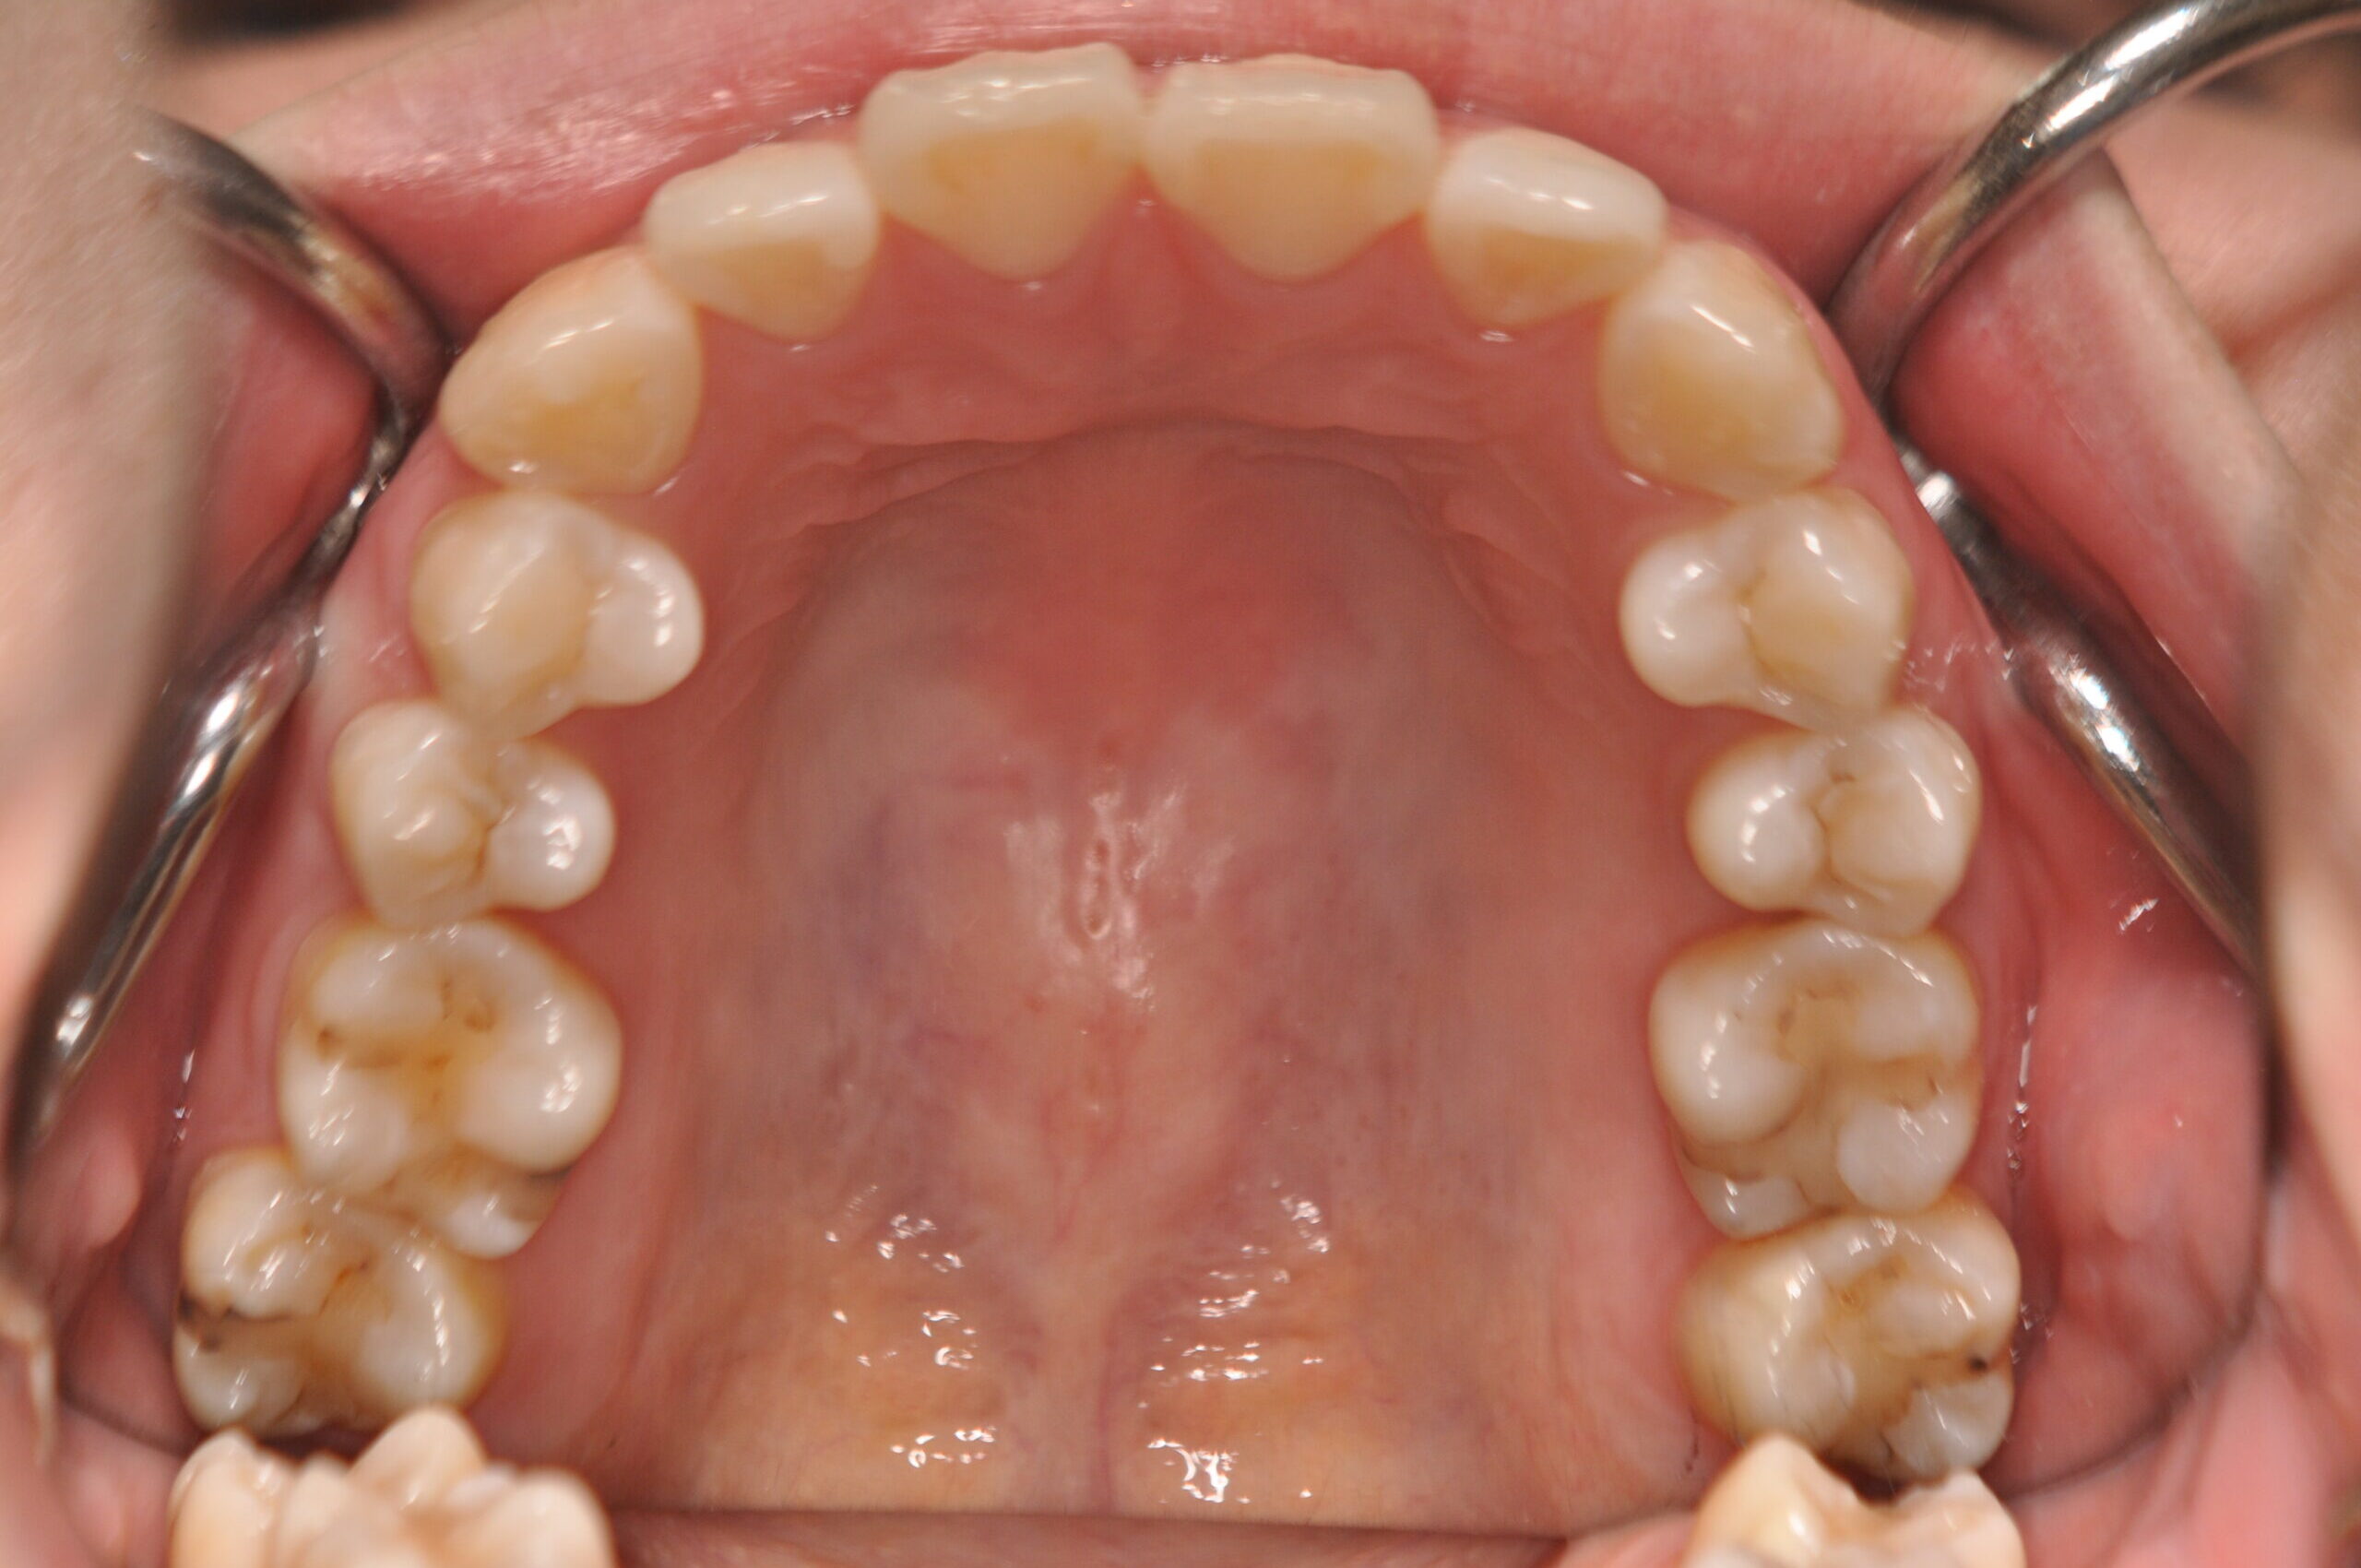

| 治療内容の詳細 | 初診時29歳の女性で、出っ歯を気にされ来院されました。 検査の結果、上顎前突を伴うアングルⅡ級1類不正咬合と診断しました。 治療としては、上顎左右第1小臼歯および下顎左右第2小臼歯をして、セルフライゲーションブラケット装置(デーモンシステム)で歯の配列を行いました。 同時に顎間ゴムにて咬合関係の改善を行いました。 この際、上顎に歯科矯正用アンカースクリューを設置し上顎前歯部後退時の土台としました。 治療期間は、2年6ヶ月でした。 |